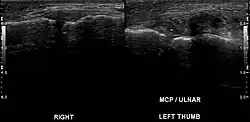

| Stener lesion on left thumb in ultrasound | |